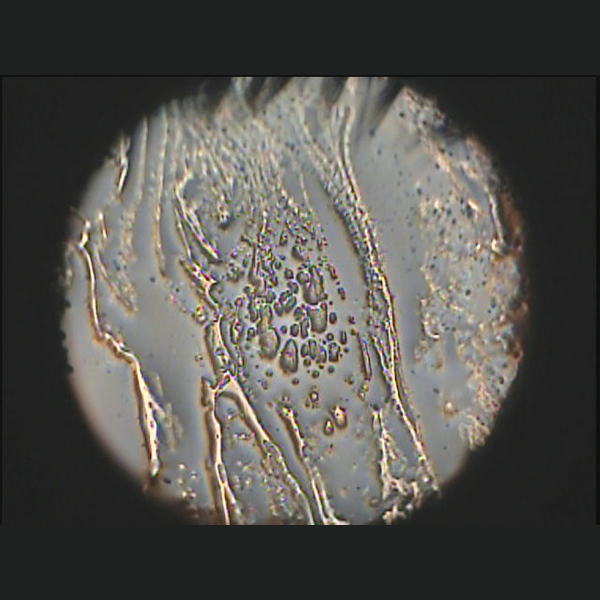

Die Kowa DR-1a ermöglicht die Beobachtung von Veränderungen des Interferenzfarbmusters, das sich auf der Lipidschicht ausbreitet. Außerdem kann diese Beobachtung auch während des Tragens von Kontaktlinsen gemacht werden.

The Kowa DR-1a enables the observation of changes in the interference color pattern propagating on the lipid layer. In addition, this observation can also be made while wearing contact lenses.